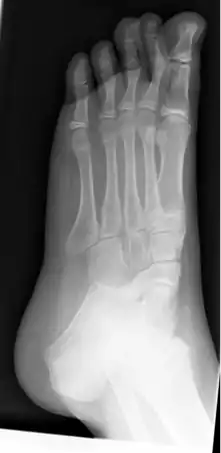

![]() Radiografía de pie izquierdo plano en un niño de 10 años. | ||